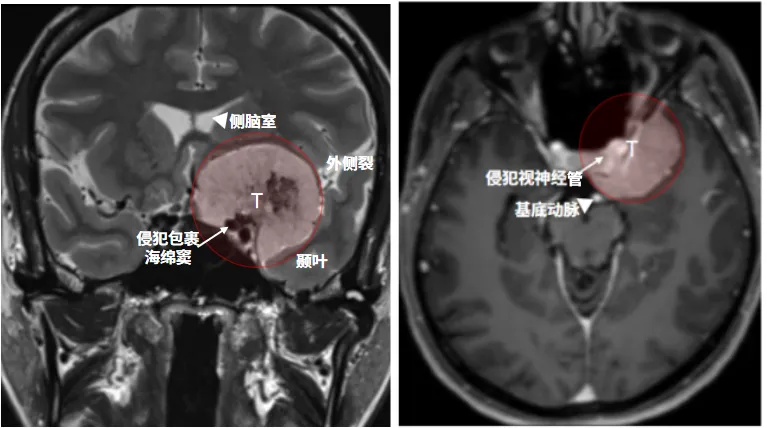

38岁的李女士怎么也没想到,一直以来的头痛和眩晕,竟是颅底深处一颗巨大肿瘤在作祟。当MRI报告显示前床突区有一个部分钙化的脑膜瘤时,她才明白为什么最近左眼的视野也突然出现“缺角”——那颗肿瘤已经像八爪鱼一样紧紧缠住颈内动脉,压迫视神经。

前床突脑膜瘤起源于前床突,常压迫并包绕邻近的神经血管结构(如颈内动脉及视神经)。由于需在保全关键结构与实现肿瘤全切之间取得平衡,此类病变对神经外科医生仍极具挑战。

大型前床突脑膜瘤手术的核心难点在于肿瘤与视神经、颈内动脉及其分支(如眼动脉、后交通动脉、脉络膜前动脉)以及垂体柄、下丘脑等重要神经血管结构的紧密粘连或包裹。肿瘤体积巨大时,往往严重压迫并推移这些结构,使得术中对它们的辨识、分离和保护异常困难,极易造成视神经损伤(永久性视力丧失)、颈内动脉或其关键穿支血管损伤(导致灾难性大出血或脑梗死)、垂体功能低下或下丘脑损伤等严重并发症。